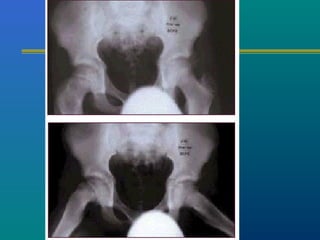

INVESTIGATIONS

X-ray --- AP & FROG LEG

LATERAL

ARTHROGRAM

ARTHROGRAM

Subchondral fracture

heralds the onset of

clinical Perthes.